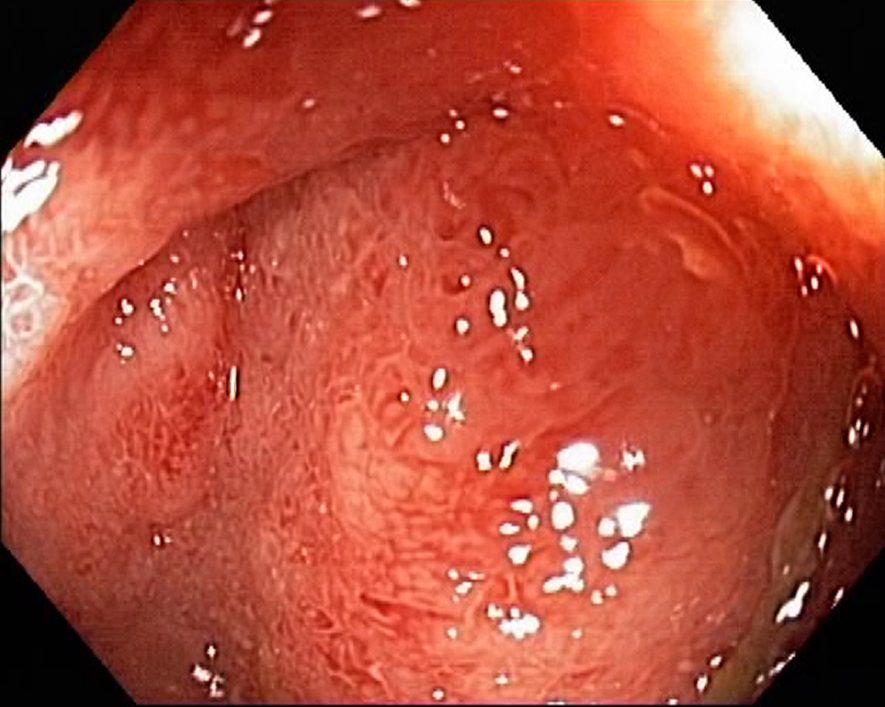

Campylobacter-Colitis